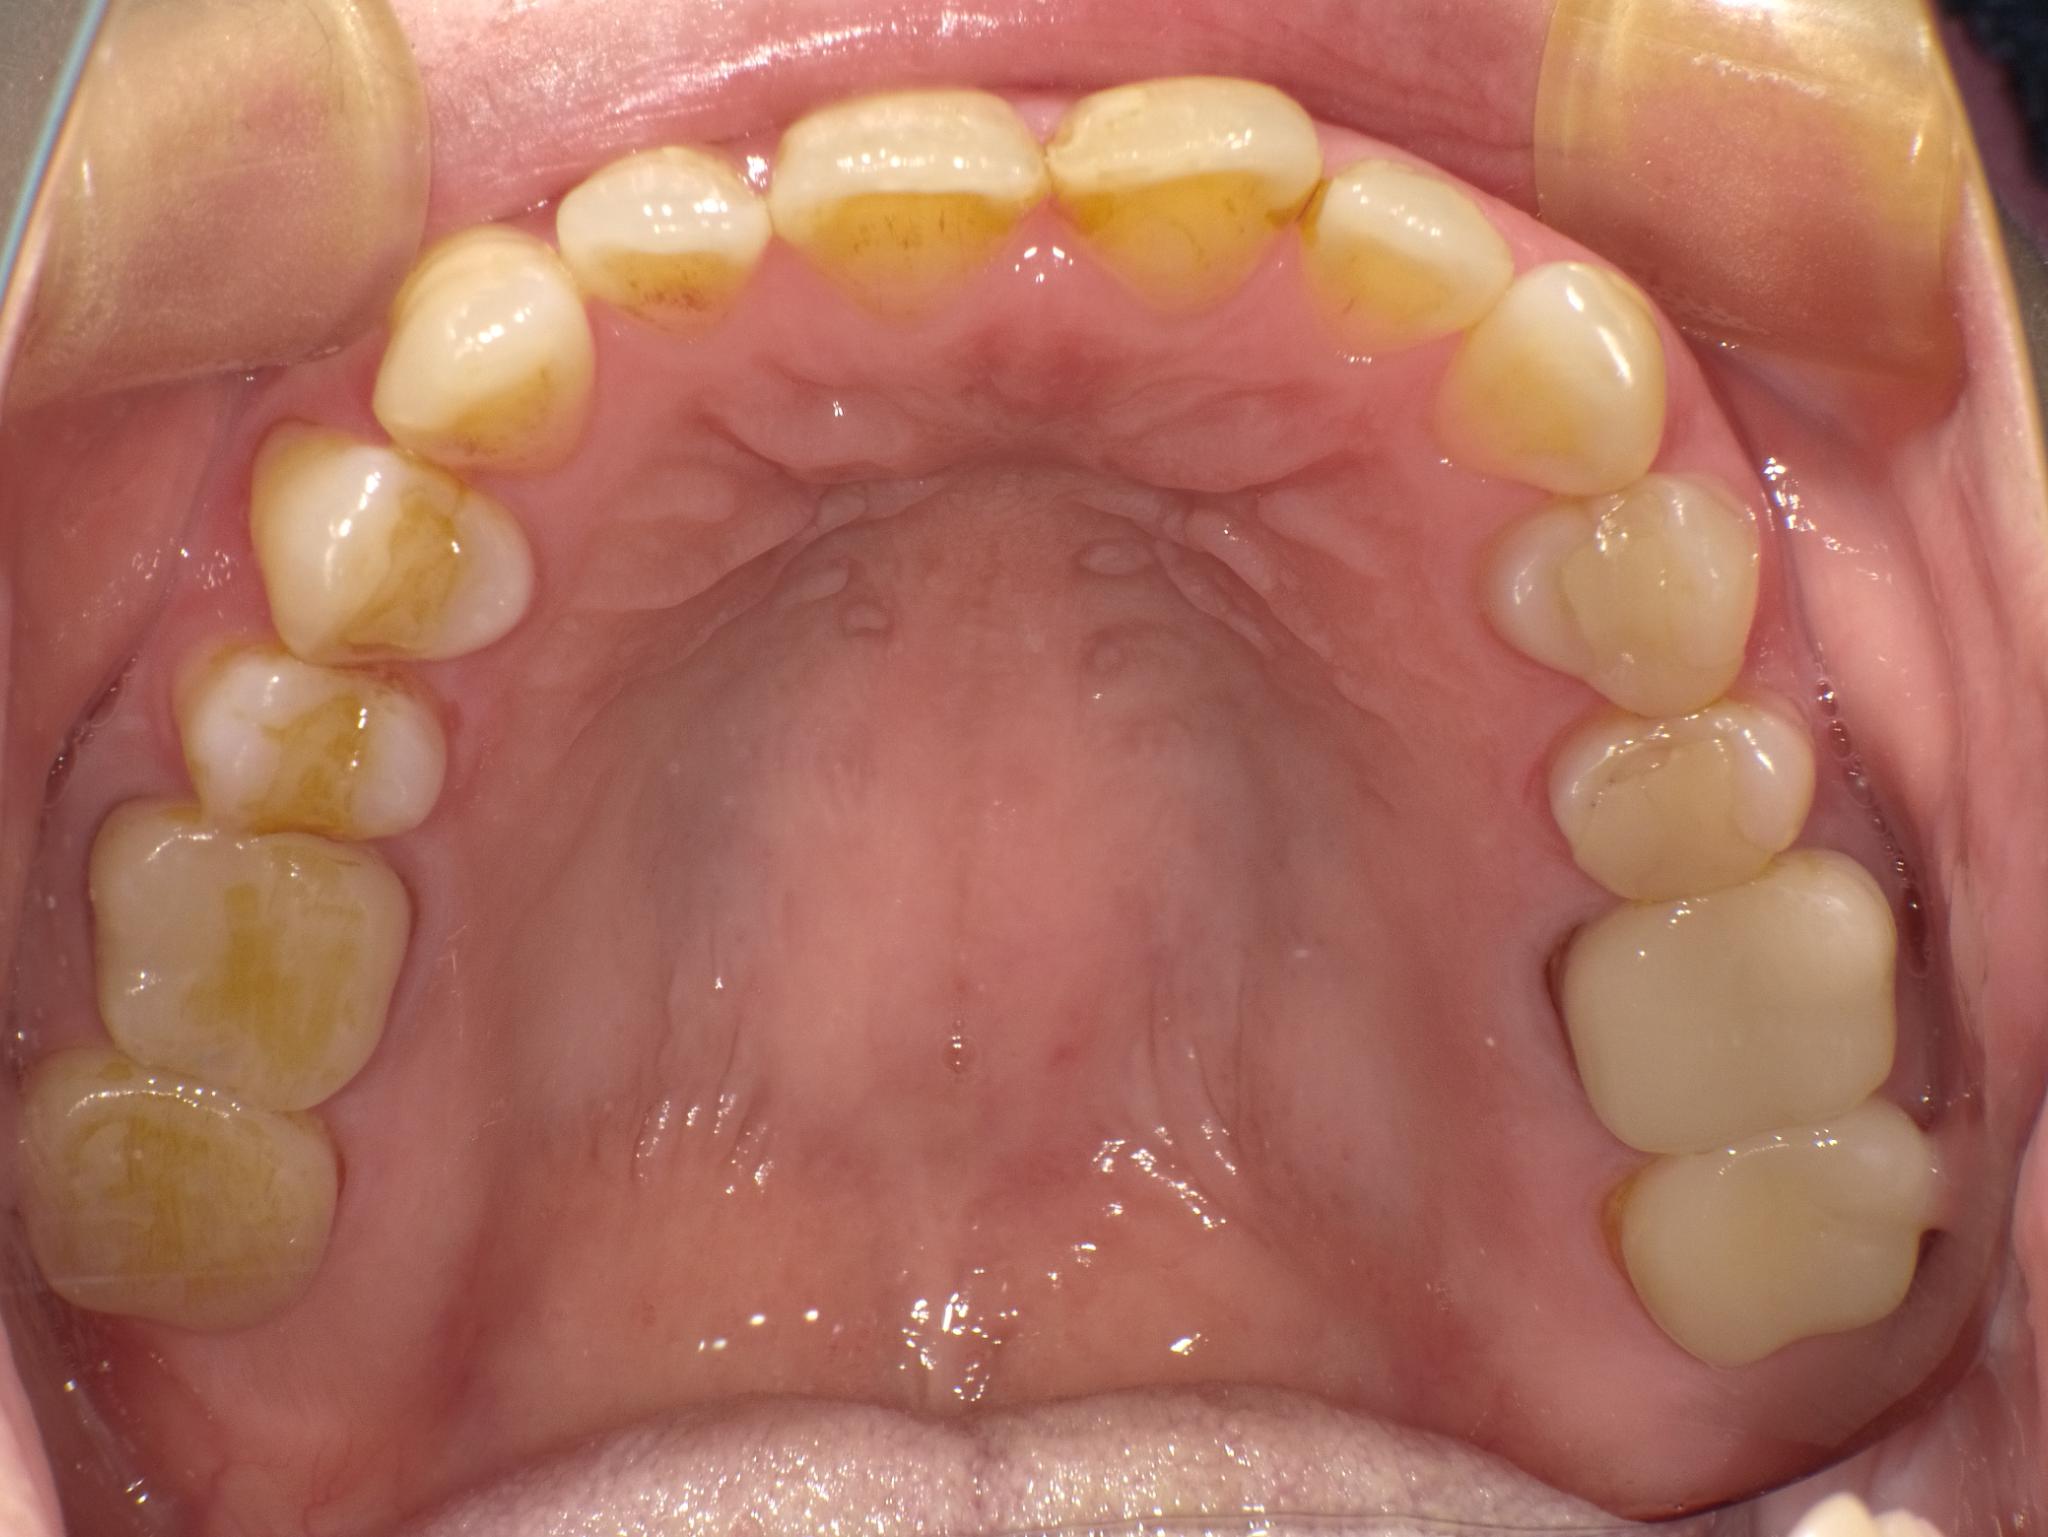

治療前

治療後

- 治療内容

- 臼歯部 クラウン4本 インレー4本

- 費用

- 580,000円(税別)〜

- 治療期間

- 約6か月

- リスク・副作用

- 50代女性。金属の詰め物がとれてしまった。頻繁に取れてしまうとのことでe.maxを選択。

セット後、破折のリスクがあるためナイトガードの使用を勧めました。